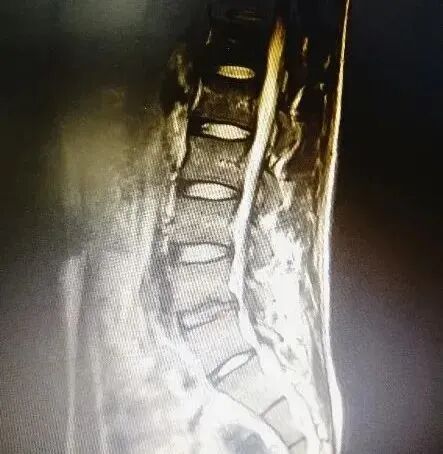

病史摘要:患者郑某,女性,49岁,饭店老板,三年前因腰背部疼痛诊断为腰肌劳损,进行相关治疗;一年前因腰痛就诊,MR诊断为:腰椎间盘膨出,腰背部筋膜炎;给予腰椎牵引及相关理疗,疼痛好转。后因腰背痛及左下肢麻木,肌力减退,日常生活活动受限,睡眠质量差及步行障碍于康复门诊就诊,MRI诊断:L5/S1椎间盘左中央旁型突出。当时结合其临床表现及相关影像资料给予其进行病情及功能状况评估,排除激光磁治疗禁忌。其主要功能障碍有:腰背部酸痛、左下肢麻木、左下肢肌力减退、日常生活受限、睡眠质量差、情绪焦躁,针对患者的功能情况,制定相应治疗目标及方案。

疼痛仪怎么回事快来看!激光磁场理疗仪疼痛的克星!_https://www.jmylbn.com_新闻资讯_第7张

该患者激光磁治疗部位:腰部、左臀部、左小腿痛点。治疗强度:65%。治疗频率:3-30Hz。治疗时间:25分钟。qd。

经过10次积极的激光磁康复治疗后,患者病情平稳,功能障碍显著改善,腰痛症状消失,下肢麻木症状明显缓解,生活质量及睡眠改善。